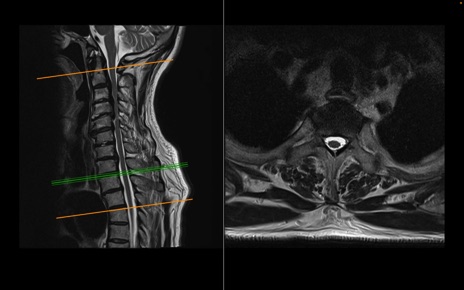

頚椎MRI

T2WI(横断像)

T2WI(矢状断像)